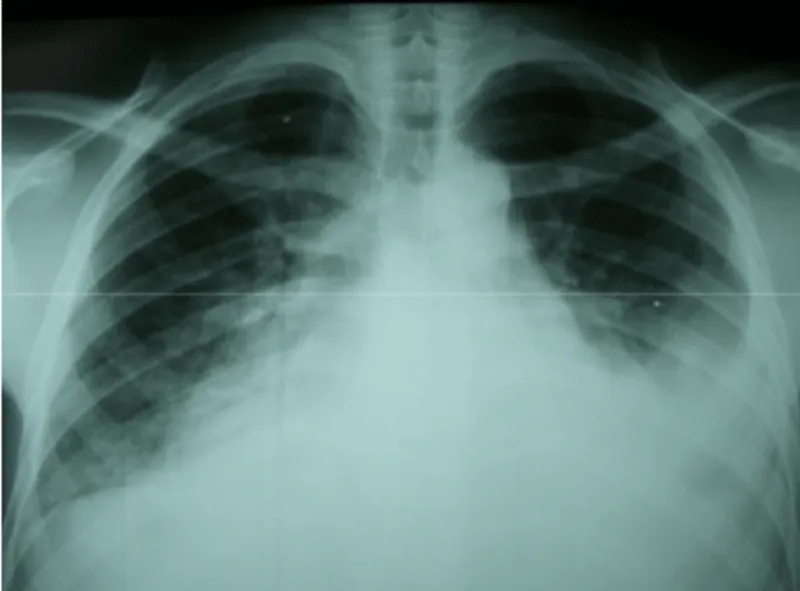

The electrocardiogram recorded a regular sinus rhythm. The X-ray showed a more marked bilateral effusion on the left, flaky opacities at the two hiles and cardiomegaly (Figure 1).

Figure 1: Chest X-ray showing alveolar edema, pleural effusion and enlarged cardiac silhouette.